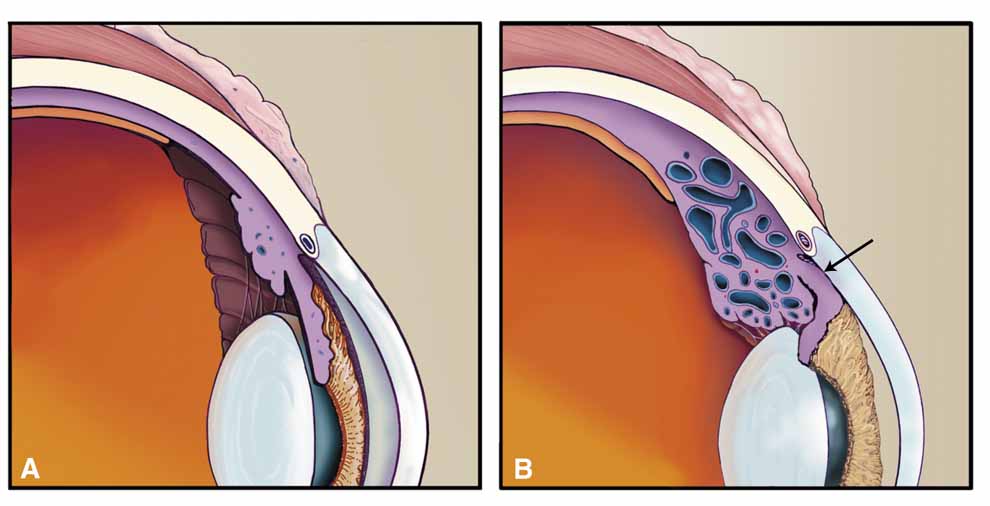

Over the past two decades silicone oil (dimethylpolysiloxane) has enjoyed a resurgence in the repair of complicated retinal detachments. In 1967, Watzke36 found no pressure elevation attributable to silicone but described droplets in the superior angle that result from silicone's lower specific gravity (buoyancy) compared with water. Silicone-induced glaucoma does occur, however, and one possible mechanism is an acute pupillary block due to the buoyancy of the silicone sometimes combined with overfilling the aphakic eye (Fig. 5). This can be averted by performing an inferior iridectomy and by paying careful attention to the silicone volume injected. A second mechanism involves chronic obstruction of an open angle by emulsified silicone microbubbles (more likely with low viscosity silicone, 1,000 centistokes, than high viscosity silicone, 12,500 centistokes) (Fig. 6), pigmented cells, and silicone-laden macrophages or silicone-induced fibrosis of the trabecular meshwork due to possible inherent fibrogenicity of this compound.37,38 Treatment of this open-angle glaucoma is generally medical, although silicone removal may be required. Although some studies have confirmed the presence of emulsified oil in the anterior chamber as a strong predictor of pressure elevation, others do not, suggesting that multiple factors are at play.39,40,41,42 Often this can only be seen on gonioscopy, and removal of the oil, if possible, is beneficial in some cases. Sometimes an expected pressure elevation that would otherwise occur may be muted by concomitant cyclitic membrane formation or hypotony associated with recurrent retinal detachment. The use of shunt procedures in this difficult glaucoma has led to the unusual complication of silicone oil escape into the subconjunctival space43,44 (Fig. 7). Whether placed superiorly or inferiorly, shunts should probably be avoided in these eyes unless the silicone oil can first be safely removed. Transscleral diode laser cyclophotocoagulation has been proven to be an excellent noninvasive option in treating these eyes for recalcitrant pressure elevation.45,46